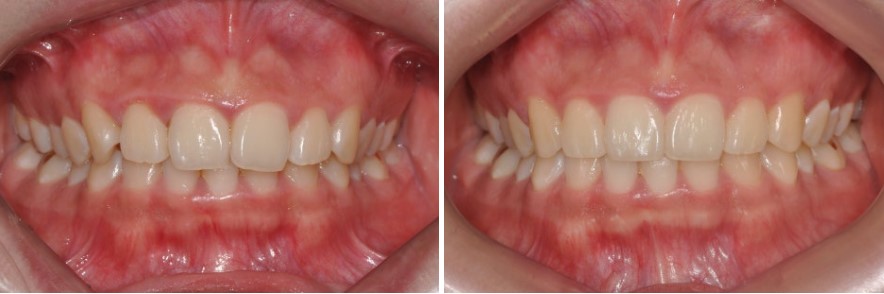

울퉁불퉁한 접촉면을 매끈하게 만들어 안정성을 높이기 위해

교정 전 치아를 자세히 보면, 서로 닿는 면(인접면)이 울퉁불퉁한 경우가 적지 않습니다.

이 경우,

정면에서 보았을 때 치아가 촘촘하게 붙어 있는 느낌이 부족할 수 있습니다.

이럴 때,

인접면을 치간삭제로 살짝 다듬어 매끈하게 만들어 주면

실제 환자 케이스로 보는 치간삭제 활용